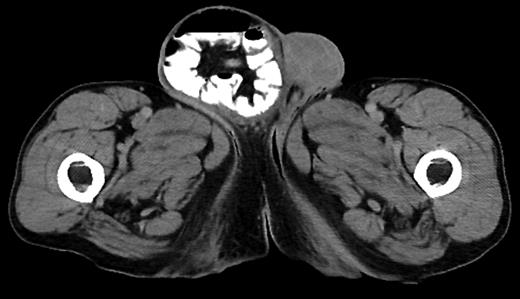

One of the primary advantages of laparoscopic surgery over open laparotomy is the reduced sequelae of having a large incision site that predisposes to potential surgical site infection that accompanies varying grades of morbidity. Smaller surgical incisions tend to have less postoperative discomfort and hospital days, minimal surgical site infection, faster return to daily activities and superior long-term cosmetic results with overall reduced financial burden and better efficacy (Figure 2) [4]. Extending a laparoscopic port incision to accommodate extraction of a large specimen depletes many of the advantages of the laparoscopic surgery. In some cases, it may be possible to dissect the specimen and remove it piecemeal; however, in many cases involving malignancies, this is undesirable and may cause seeding of cancer cells. Combining multiple surgeries together allows the surgeon to combine common steps between the various procedures. For example, anesthesia only needs to be given once, fewer incisions are needed and only a single hospital visit is required for the patient. This greatly reduces the cost of the procedure for both the patient and the hospital.